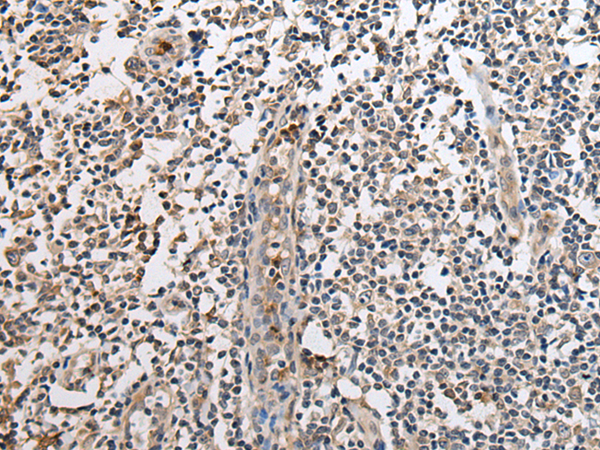

ELISA, IHC

IHC positive control:

Human brain and human tonsil

IHC Recommend dilution:

25-100